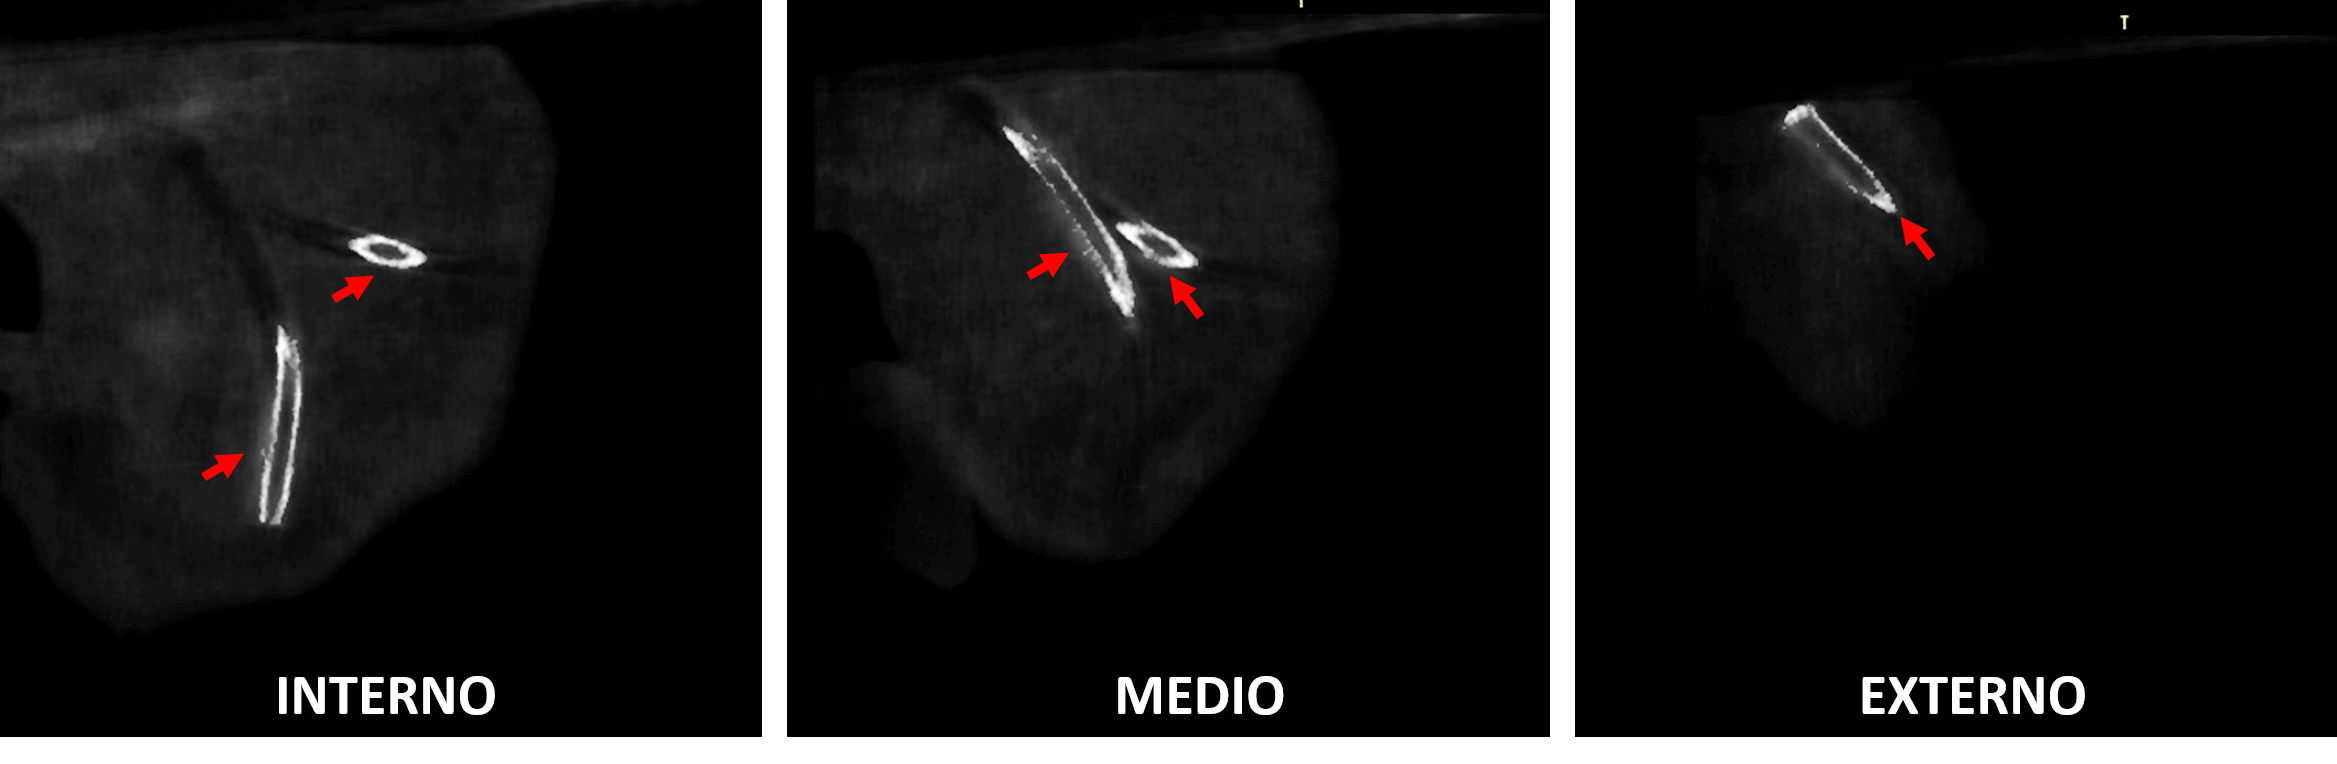

Fig.4

En la reconstrucción tridimensional (Fig.4) se observa se forma didáctica el hallazgo tomográfico el cual se observa que hace una curva a nivel superior compatible con un catéter.